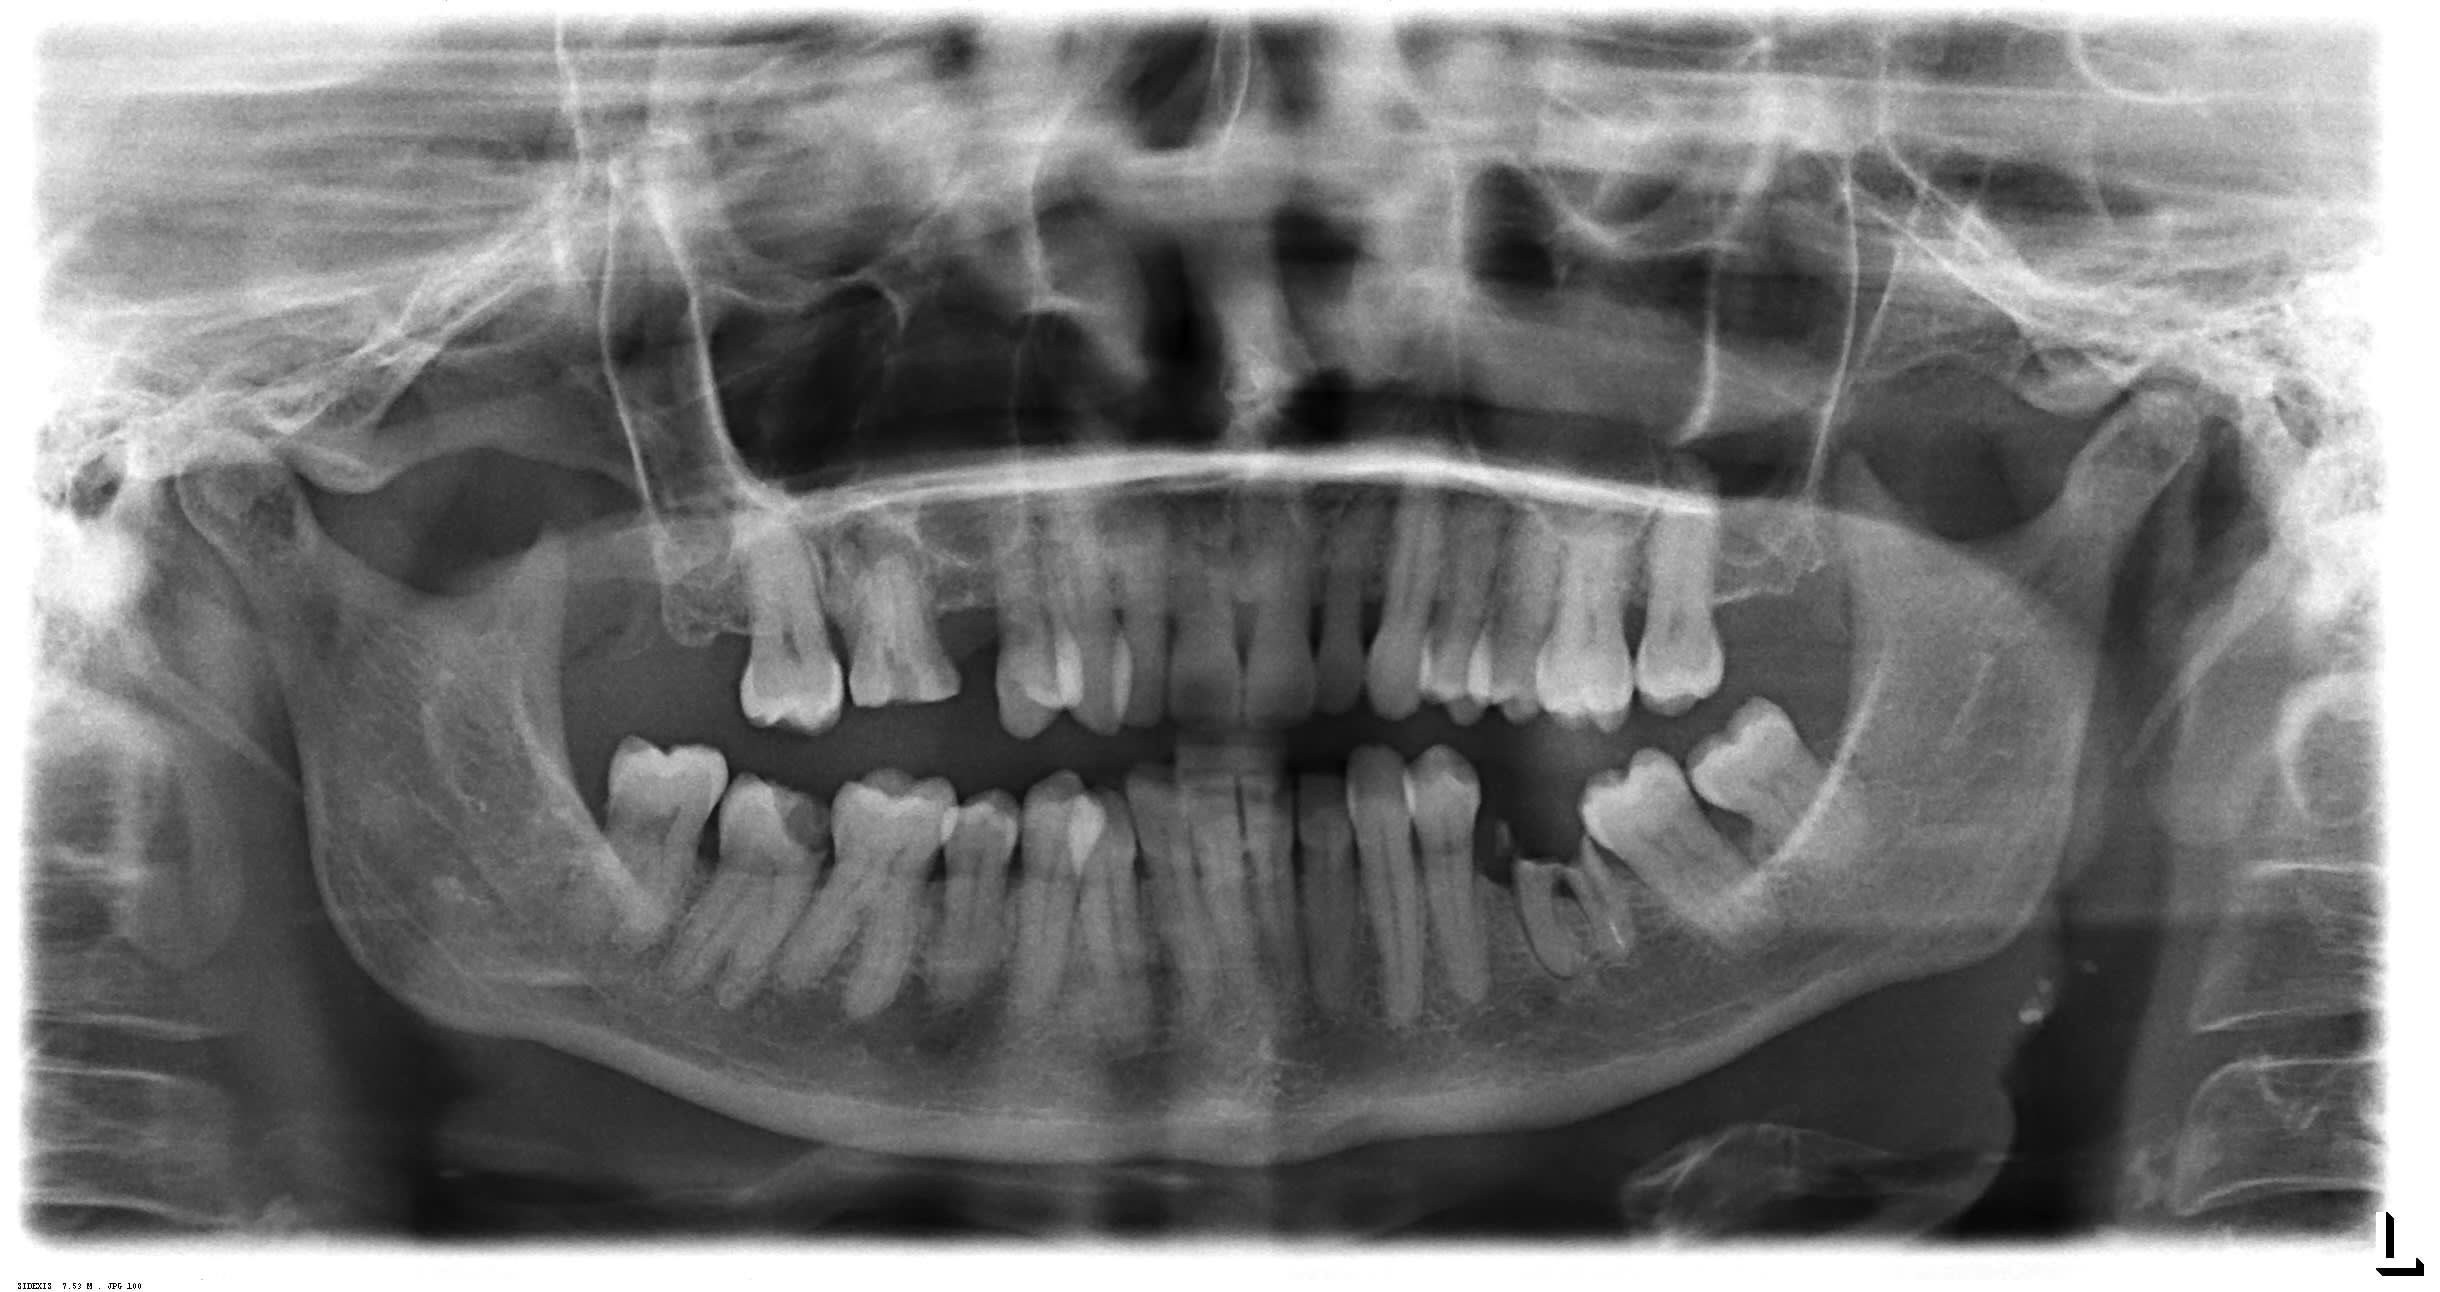

Que feriez vous pour cette patiente de 70 ans sans gros problèmes de santé au niveau de sa 16?

Tentez vous le RTE?

Technique "Enlaye"?

Extraction?

Je vous joins la RVG, la Pano et la 3D...

Extraction sans hésiter , rupture de la corticale et du plancher sinusien avec certainement CBS

Vu la proximité de 16 avec le sinus et l'absence d'inflammation de la muqueuse sinusienne au cone beam,on peut conclure à l'absence d'inflammation au niveau de la lésion, donc c'est une lésion kystique.

donc avulsion.

Mais rien ne t'empêche d'exploiter les infos disponibles (absence d'inflammation muqueuse sinusienne et proximité radiculaire). L'égression de la dent avec cette lésion n'est pas anodine non plus.

Dans ce cas précis, la probabilité de succès du RTE me paraît insuffisante, ce n'est que mon avis.